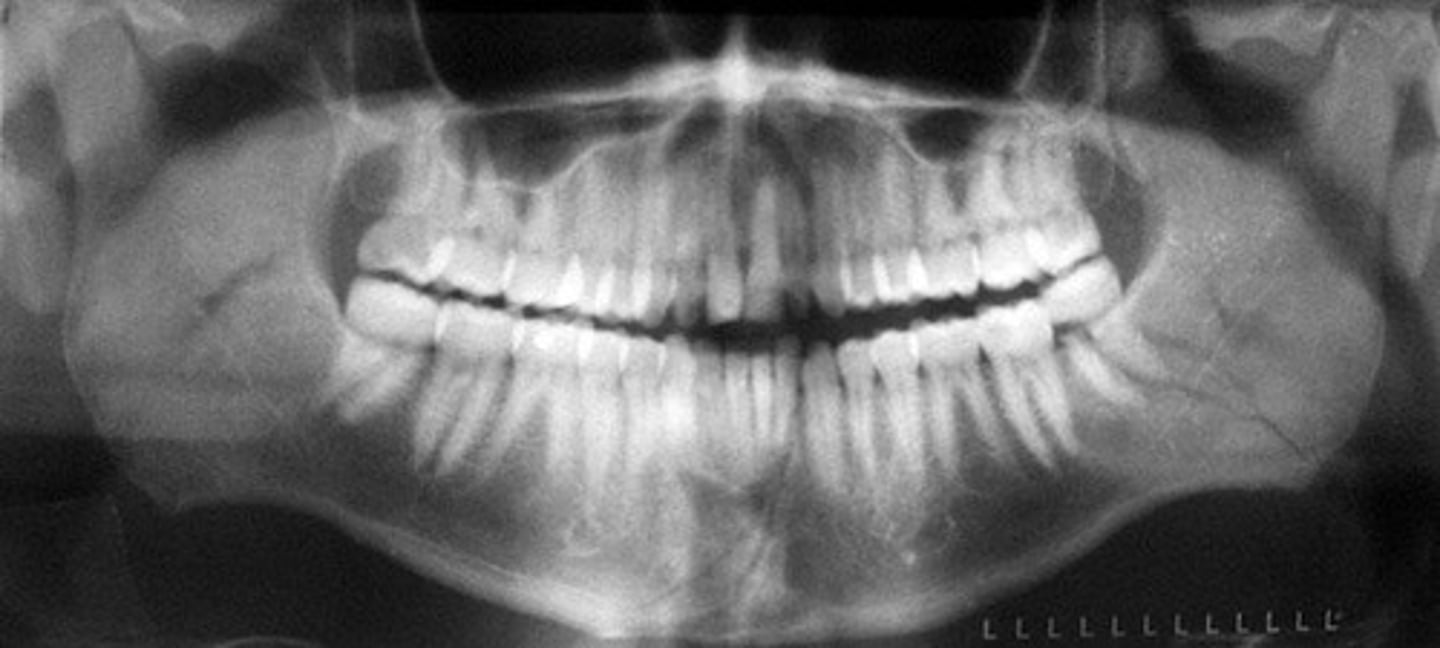

Panoramic x-ray

to identify various issues including impacted teeth, jaw and sinus problems, cysts, tumors, and gum disease